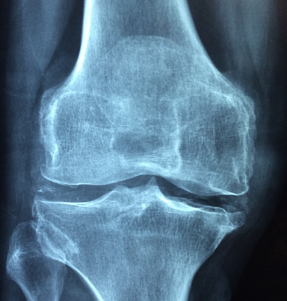

골다공증은 뼈의 밀도가 낮아지고 강도가 약해져 골절이 일어날 가능성이 높은 상태를 의미합니다. 골다공증의 생기는 이유는 여러 가지 원인이 있으며 대표적으로 유전적 요인, 조기 폐경, 흡연 및 음주, 그리고 류머티즘 관절염 등이 있습니다. 골다공증의 증상은 일반적으로 뚜렷한 증상이 없지만 작은 외부 충격으로도 골절이 생길 수 있으며 골절이 발생한 부위에 따라 여러 가지 증상이 나타날 수 있습니다. 골절은 신체 어느 부분에서 일어날 수 있지만, 특히, 손목뼈, 척추, 고관절(대퇴골)에서 골절이 자주 발생하게 됩니다.

골다공증은 뼈 조직의 강도가 약해져 뼈가 약해지는 질병이다. 이는 뼈 조직의 손상과 재생 과정의 불균형으로 인한 뼈 손실입니다.